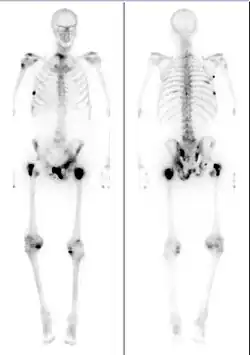

The extent of cancer spread is assessed by MRI or PSMA scan – a positron emission tomography (PET) imaging technique where a radioactive label that binds the prostate protein prostate-specific membrane antigen is used to detect metastases distant from the prostate.[30][24] CT scans may also be used, but are less able to detect spread outside the prostate than MRI. Bone scintigraphy is used to test for spread of cancer to bones.[30]